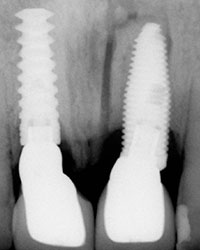

Al término de la distracción dejamos pasar tres meses con una férula en acrílico. En el diente 21 que habíamos visto en la radiografía un problema de un absceso periapical y periodontal.

Dejamos que el implante se oseointegre para terminar con la rehabilitación protésica.